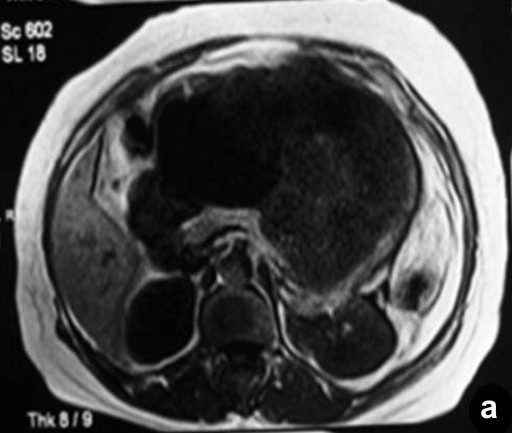

Routine laboratory investigations were within normal limits except for anemia (hemoglobin: 8 g/dL; reference range: 12-15 g/dL). A contrast-enhanced computerized tomogram of the abdomen (Figure 1) revealed a large heterogeneously enhancing mass of mixed echogenicity (mostly cystic with a few solid areas), measuring 35x30x25 cm, in the region of the body and the tail of the pancreas. The mass did not communicate with the main pancreatic duct. There were no ascites or lymphadenopathy. On magnetic resonance imaging, the mass was hypointense on T1-weighted imaging and hyperintense (cystic) on T2-weighted imaging with hemorrhagic and calcific foci (Figure 2). The possibility of a malignant cystic neoplasm of the pancreas was considered. Upper gastrointestinal endoscopy and colonoscopy showed no abnormalities. At laparotomy, a large mass was found to arise from the body and tail region of the pancreas. There was no attachment to the stomach, and the colon was stretched over the mass. There was no evidence of peritoneal dissemination. To achieve a R0 resection, a distal pancreatectomy, splenectomy and left hemicolectomy were performed.

Figure 2. Magnetic resonance imaging showing the mass to be hypointense on T1-weighted imaging (a.) and hyperintense on T2-weighted imaging (b.). |